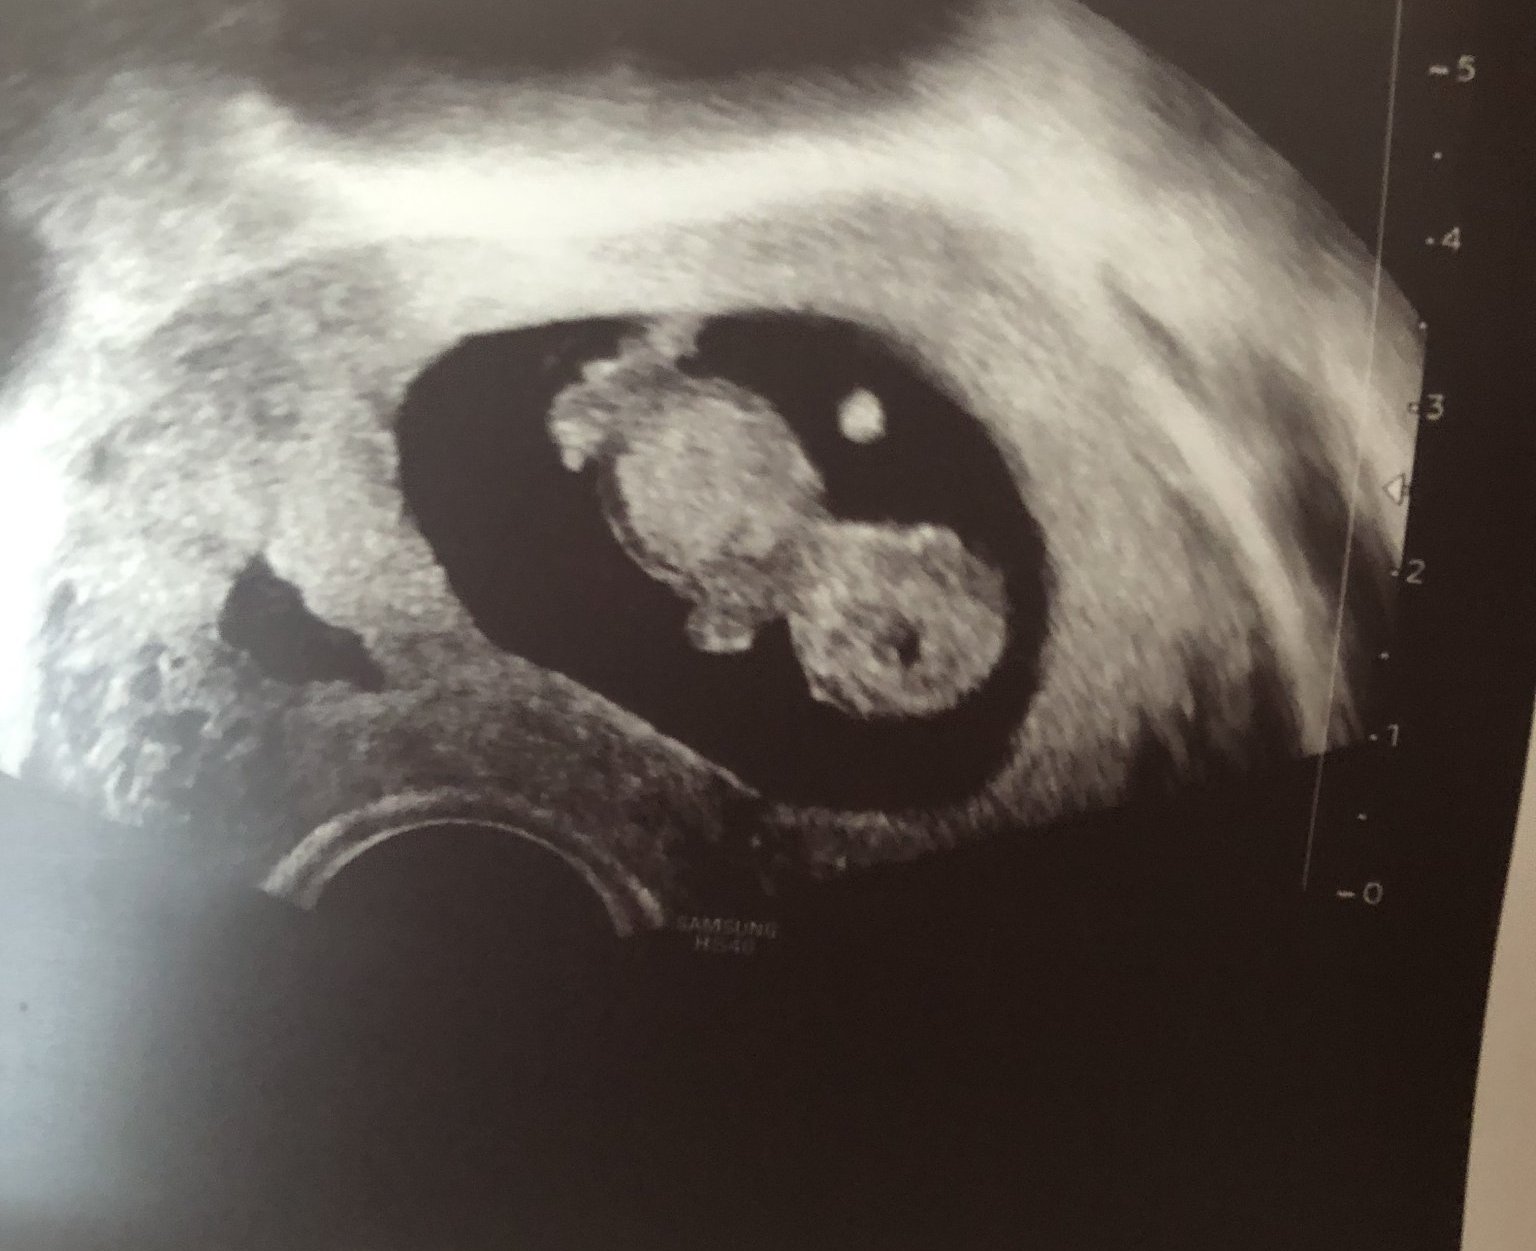

Да ви покажа едно “кюфтенце” както му казвам на 10 + 3 г.с.